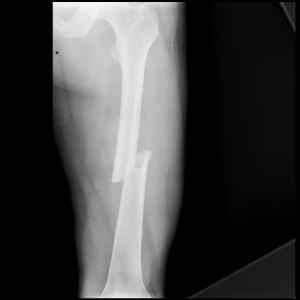

Mid Shaft Femur